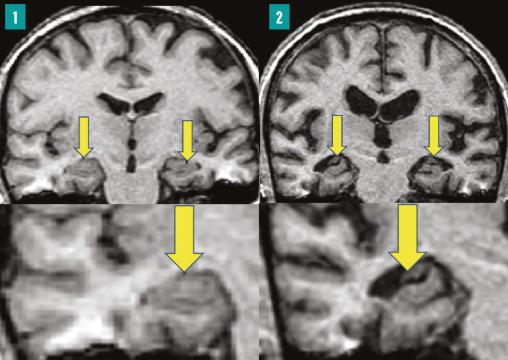

IRM cérébrale en séquence FLAIR. Coupes hippocampiques.

Colonne 1 : hippocampes normaux (flèches).

Colonne 2 : hippocampes atrophiés (flèches), dont témoigne l’élargissement de la corne temporale, signes d'une maladie d'Alzheimer